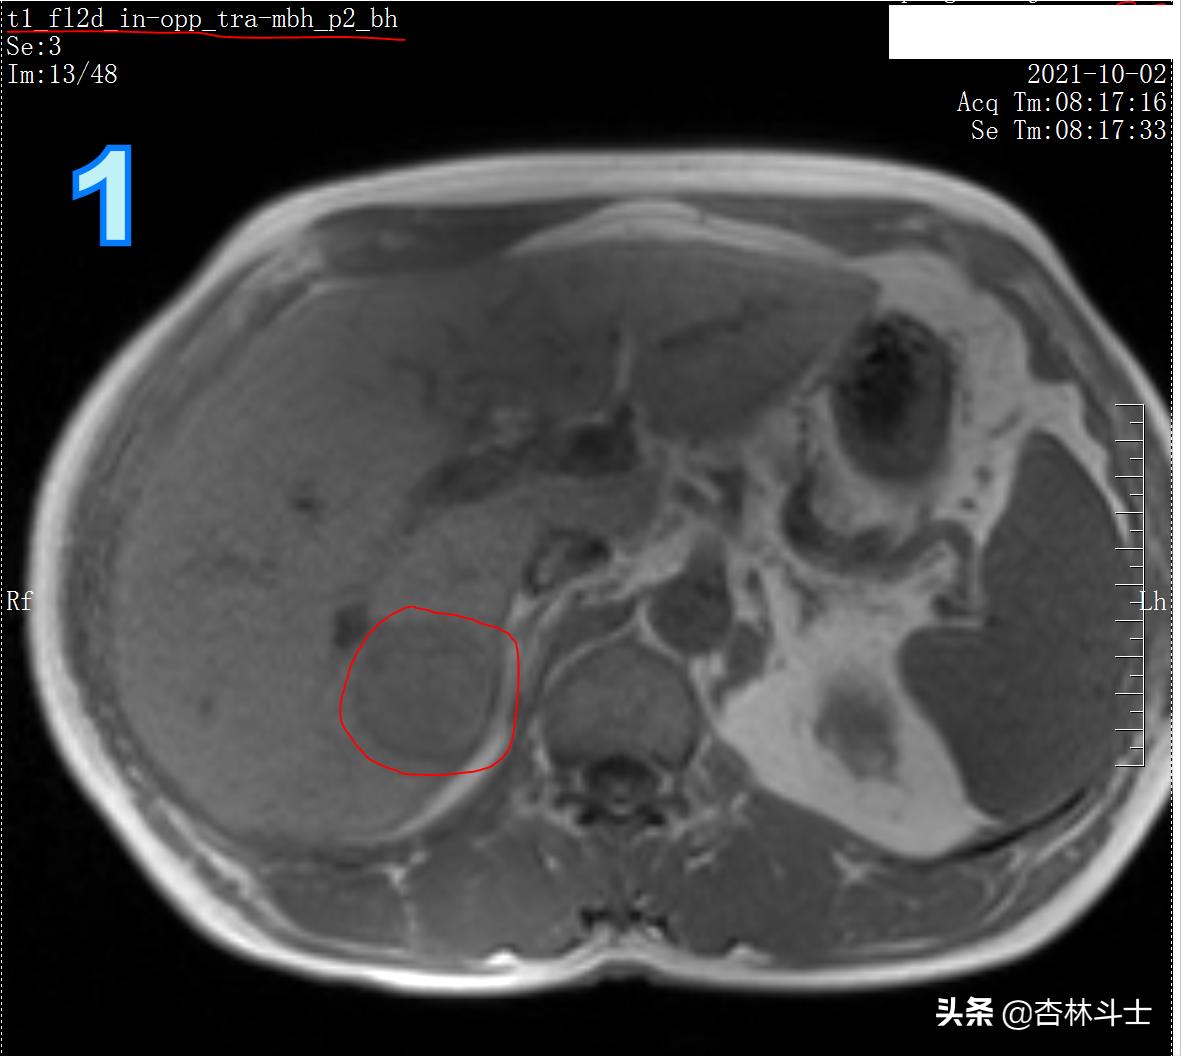

图1 T1加权同相位,同一个3T磁共振机器,与01月22日的信号明显不同

图1-3为T1加权图像,同一台3T磁共振机器上做的,与1月22日的信号明显不同,说明病灶里面的成分有所变化。